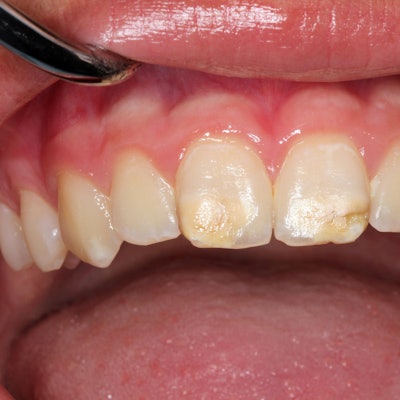

Der Siebenjährige habe zuvor über Kieferschmerzen und Schwellungen geklagt, ohne dass die im rechten Unterkiefer versteckten und nicht sichtbaren Zähne entdeckt worden seien, sagte Ramani weiter. Demnach litt er an einem sogenannten Odontom, einer gutartigen Geschwulst, die viele rudimentäre Zähne enthalten kann. Ungewöhnlich ist jedoch die Zahl. 2014 waren einem Teenager im westindischen Mumbai nach Angaben des Krankenhauses 232 Zähne entfernt worden.